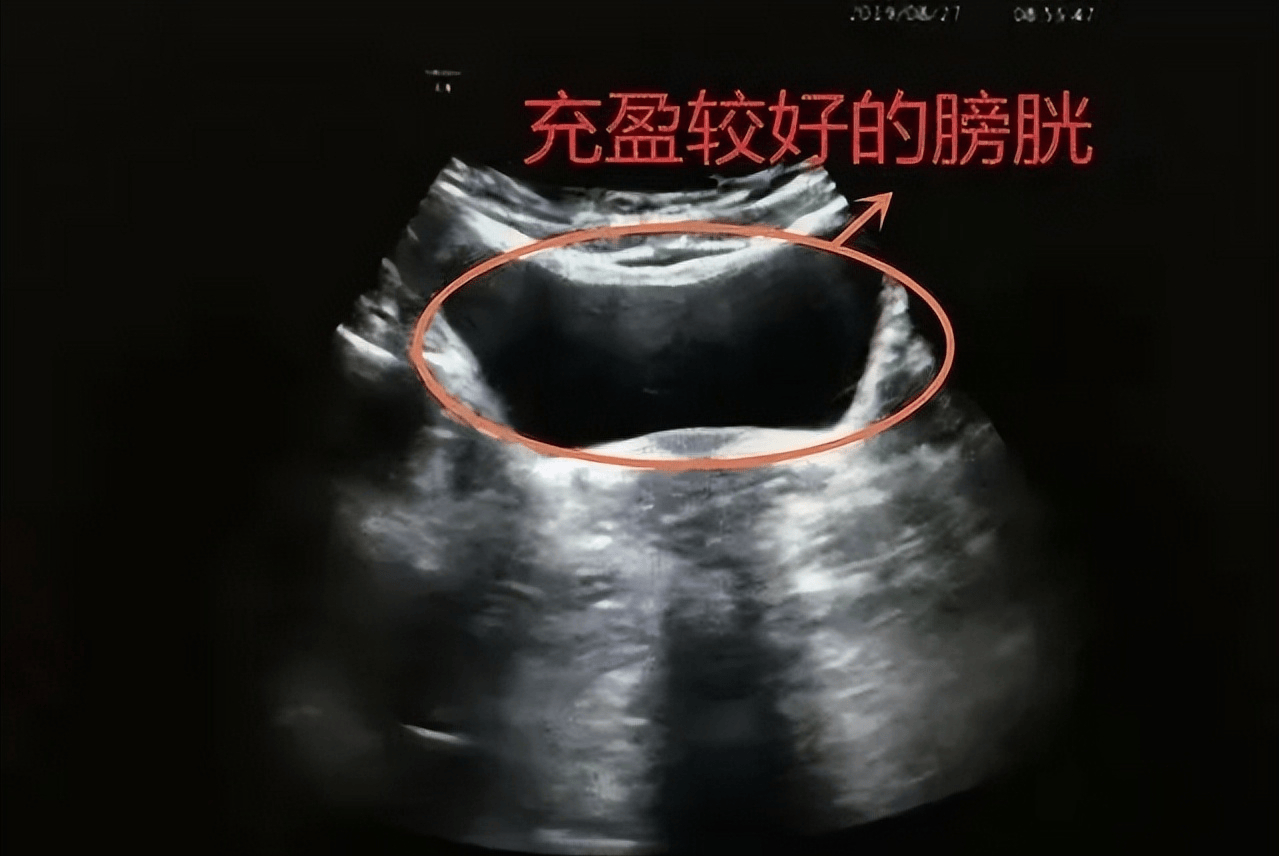

他召集开会,开门见山:“我们重新做了尸检,发现死者膀胱里有300毫升尿液。

”

“对50多岁的人来说,起夜很正常。

膀胱这么胀,不适合调情。

我们推测,死者应该是睡着后被尿憋醒,突然发现有人入室,才被杀。

另外,技术人员检查了死者隐私部位,没有任何分泌物痕迹——说明根本没发生过关系。